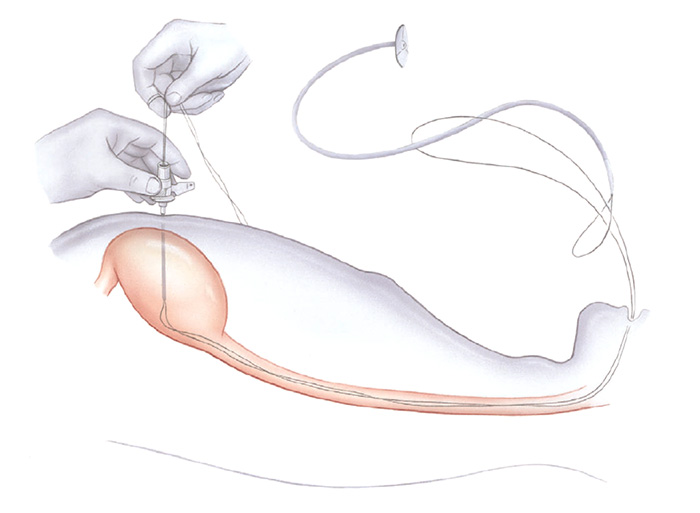

Pacientes que têm o objetivo de emagrecer, podem ter como alternativa a passagem de um balão intragástrico. A passagem do balão é realizada por endoscopia e o procedimento dura cerca de 20 a 30 minutos.

Passagem de Balão Intragástrico

1. O balão intragástrico é introduzido desinsuflado durante a endoscopia e colocado no estômago.

2. Um líquido azul (azul de metileno diluído em soro fisiológico) é colocado dentro do balão através de uma válvula. O volume varia entre 500-700 ml.

3. O aparelho de endoscopia é removido e o balão intragástrico pode ser deixado por um período de até 6 meses.

Pacientes que têm o objetivo de emagrecer, podem ter como alternativa a passagem de um balão intragástrico. A passagem do balão é realizada por endoscopia e o procedimento dura cerca de 20 a 30 minutos.

Passagem de Balão Intragástrico

1. O balão intragástrico é introduzido desinsuflado durante a endoscopia e colocado no estômago.

2. Um líquido azul (azul de metileno diluído em soro fisiológico) é colocado dentro do balão através de uma válvula. O volume varia entre 500-700 ml.

3. O aparelho de endoscopia é removido e o balão intragástrico pode ser deixado por um período de até 6 meses.